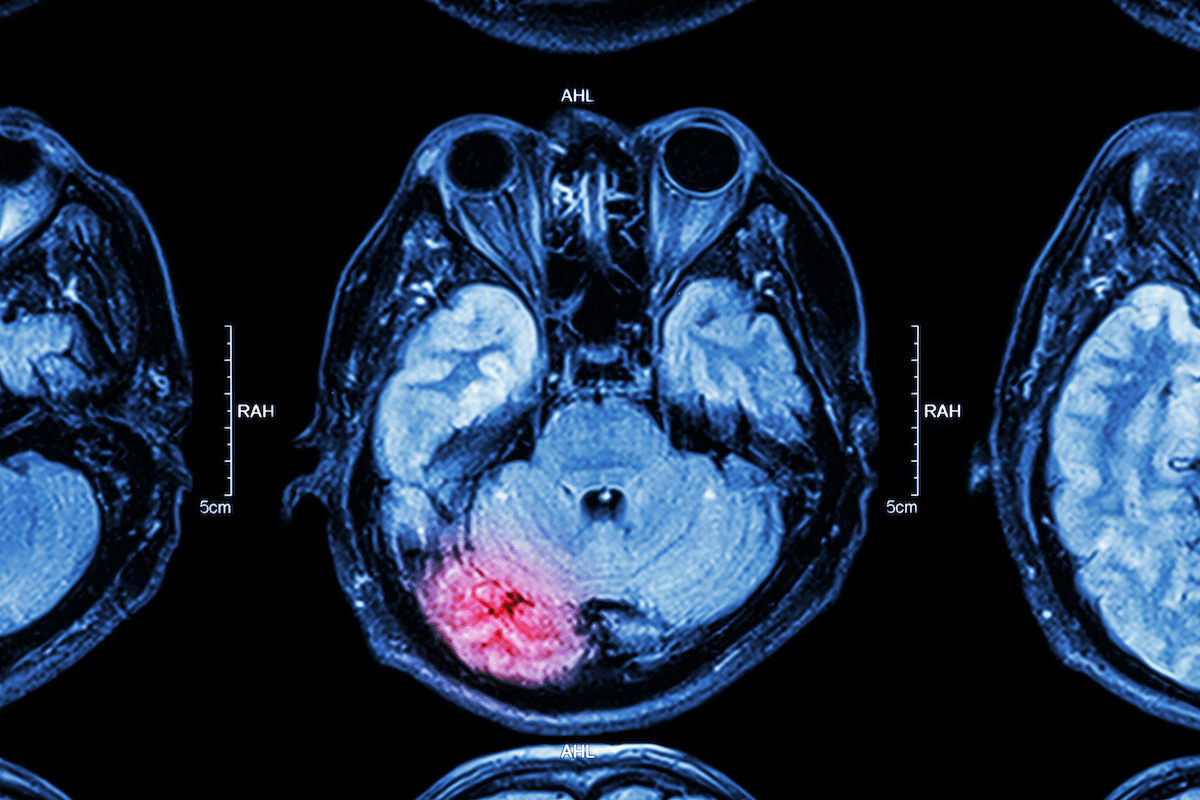

How is cerebellar atrophy diagnosed?

Diagnosis involves clinical evaluation, imaging studies like MRI, and sometimes genetic testing. Other tests may be used to find the underlying cause.